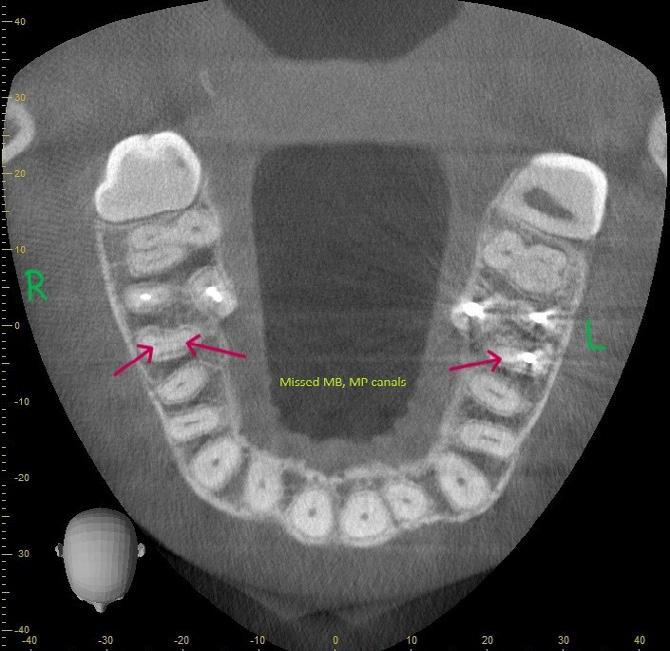

A 37-year-old female (Mrs H. K.) was referred for endodontic assessment and management of teeth 16, 26 and 46 before orthodontic space management. Clinical and radiographic evaluation, including CBCT scanning, revealed that teeth 16

and 26 were asymptomatic clinically; however, imaging confirmed the presence of missed mesiopalatal root canals, short obturation lengths in other canals, and distinct periapical radiolucencies. Both maxillary molars were diagnosed as previously root-filled with inadequate quality, exhibiting infected rootcanal systems (RCS), chronic apical periodontitis, and external apical inflammatory resorption associated with restoration breakdown, cracks, and recurrent decay. Tooth 46 shared similar diagnostic features but also demonstrated concurrent periodontal involvement, indicating a combined endodontic–periodontal lesion.

Figure 1: CBCT sagittal section demonstrating periodontal bone loss involving the furcation area of tooth 46.

Figure 2: CBCT transverse section demonstrating bone loss involving the furcation area of tooth 46.

Figure 3: CBCT transverse section demonstrating missed mesial root canals in teeth 16 and 26.